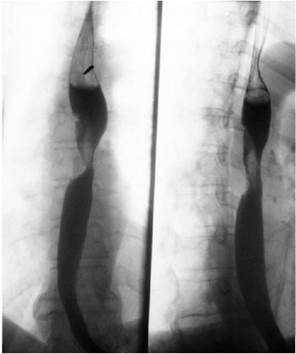

Больной 25 лет лет был избит 3 дня назад. На рентгене:  Ваш полный диагноз: //

Ваш полный диагноз: //

+ Тупая травма грудной клетки. Гемопневмоторакс справа.//

Открытая травма грудной клетки. Гемопневмоторакс справа.//

Тупая травма грудной клетки. Гемоторакс справа.//

Тупая травма грудной клетки. Гемопневмоторакс справа. Травматический шок 1 ст.//

Т Тупая травма грудной клетки. Гемоторакс справа. Травматический шок 2 ст.